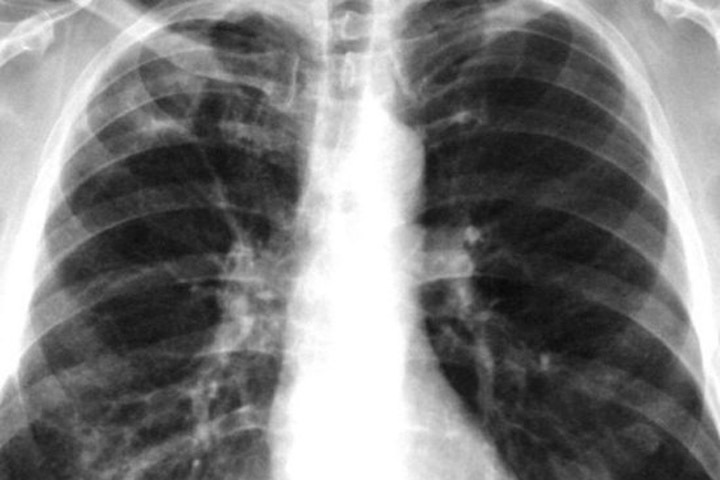

Алтайский депутат предрекает эпидемию туберкулеза в Рубцовске

Член фракции КПРФ в горсовете Рубцовска Надежда Дрюпина заявила о возможной эпидемии туберкулеза в городе после закрытия диспансера. По ее словам, люди умирают, не дождавшись медицинской помощи.

Дрюпина заявила, что проблема с закрытием противотуберкулезного диспансера в Рубцовске не была услышана «чиновниками разного уровня», хотя в городе за полгода умерли 23 человека. Если вопрос не будет решено, то депутат не исключает эпидемию туберкулеза в городе.

«В городе с населением 143 тыс. человек на учете в тубдиспансере состоят 1500 больных пациентов, из них 400 — „активных“, 215 — с открытой формой этого тяжелого заболевания, — приводит слова Дрюпиной крайком КПРФ. — А между тем краевое министерство здравоохранения во главе с Дмитрием Поповым не планирует возобновлять работу круглосуточного противотуберкулёзного стационара в Рубцовске».